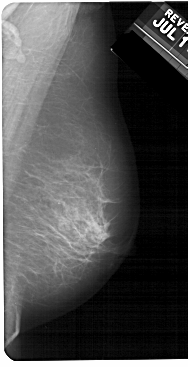

A_1243_1.LEFT_MLO

LEFT_MLO LINES 5491 PIXELS_PER_LINE 2761 BITS_PER_PIXEL 12 RESOLUTION 43.5 OVERLAY